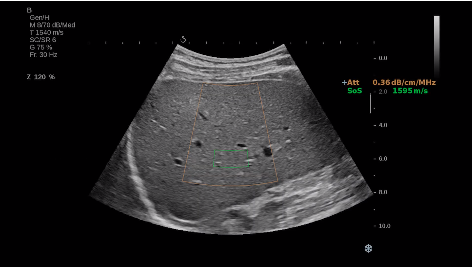

法國(guó)聲科影像(SuperSonic Imagine,SSI. Euroniex:FR0010526814)近日發(fā)表公告,宣布其研發(fā)的新一代“極速”超聲成像平臺(tái)(UltraFast Imaging),首次實(shí)現(xiàn)了肝臟的多項(xiàng)超聲定量評(píng)估新指標(biāo)同步檢測(cè),包括:Att PLUS,SSp PLUS和Vi PLUS等,基本涵蓋肝臟相關(guān)病理變化指征的如纖維化、脂肪變、炎癥等。據(jù)悉,此多項(xiàng)新技術(shù)新將搭載于新Aixplorer系列E超系統(tǒng)。

E超相關(guān)技術(shù)已被多項(xiàng)多中心大樣本研究證實(shí)對(duì)于肝纖維化無創(chuàng)評(píng)估有重要意義,同時(shí)也可全面應(yīng)用于乳腺、甲狀腺、肝臟、前列腺、肌骨、婦科等全身各組織器官的定量評(píng)估和鑒別診斷。在慢性肝臟方面,聲科E超的肝臟相關(guān)定量診斷技術(shù)集,于2018年獲得美國(guó)FDA認(rèn)證,成為FDA歷史上首次獲批的單病種超聲全面定量解決方案。

E超是在原有B超、彩超(彩色多普勒CDFI)基礎(chǔ)上研發(fā)成功的新一代超聲剪切波彈性成像系統(tǒng),是一種能夠全面應(yīng)用于表淺組織、腹部臟器,血管等方面的組織彈性成像技術(shù)。根據(jù)組織硬度彈性值的不同,有效鑒別實(shí)性腫瘤的良惡性。對(duì)于惡性病變的診斷具有較高的特異性和敏感性,尤其對(duì)于甲狀腺、乳腺、前列腺等小器官,能夠完成常規(guī)超聲不能完成的組織定量分析,可以實(shí)時(shí)、全幅、全定量獲得組織彈性(硬度)信息,為鑒別腫瘤的良惡性提供客觀、量化的診斷依據(jù)。